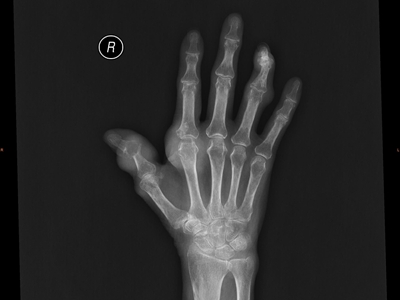

痛风病程较长,常反复发作而迁延不愈形成痛风石,是痛风的特征性临床表现,常见于指关节、第一跖趾关节、耳廓等处。外观为隆起、大小不一的不规则的黄白色赘生物,表面菲薄,破溃后排出白色粉状或糊状尿酸盐结晶物,经久不愈,但较少继发感染。部分患者伴有肾结石及肾脏病变。